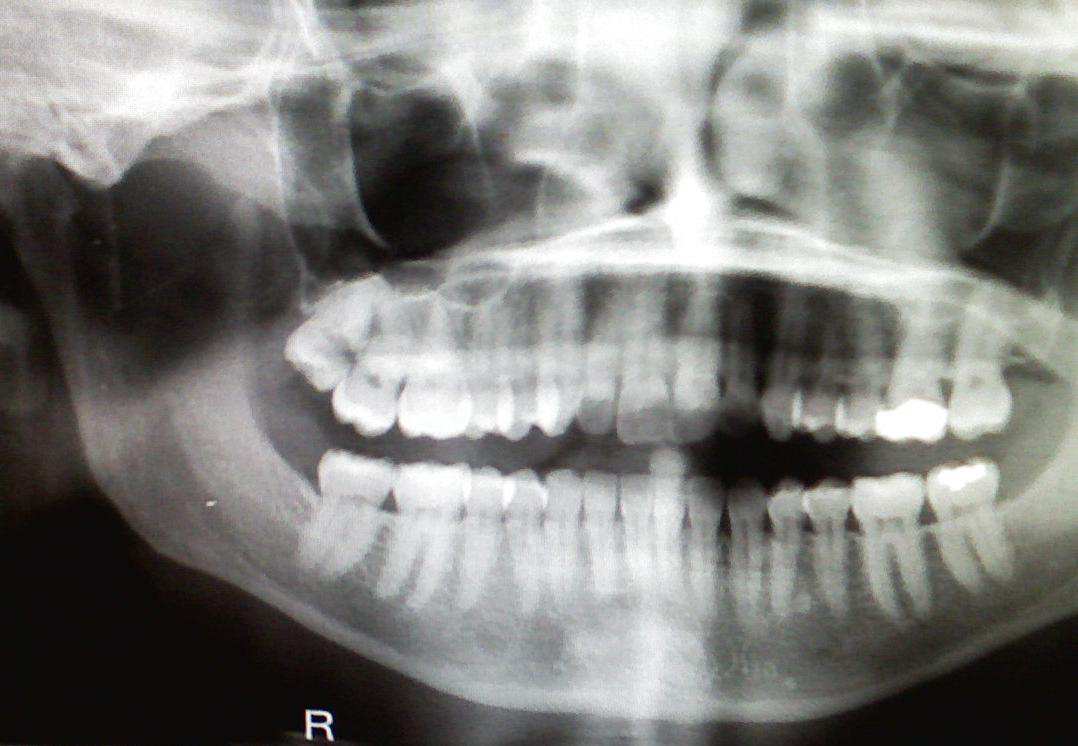

FileClassic keratocystic odontogenic tumour.jpg Wikimedia Commons Dental X-Rays Brain Cancer Ionizing radiation is a consistently identified and potentially modifiable risk factor for meningioma, the most frequently reported. Dental X-Rays Brain Cancer.